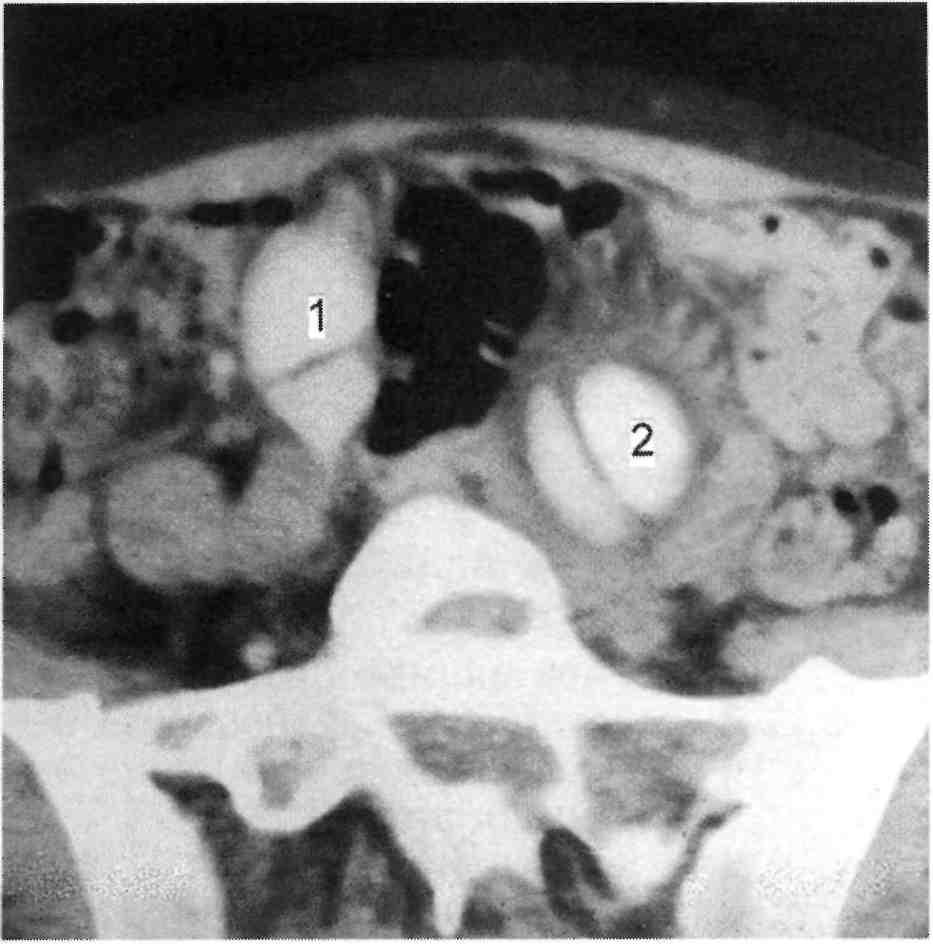

КТ ретроперитонеального фиброза: Изображения и диагностика